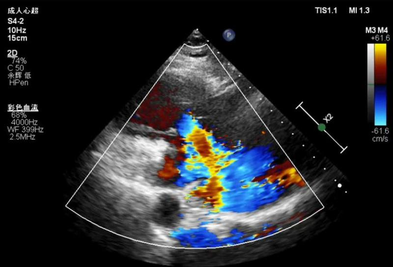

宝山首例!家门口的“心门修复师”为心衰患者重焕心活力 家住宝山区大场镇的68岁市民李女士,因反复胸闷、气促伴双下肢水肿9个月,长期受心力衰竭困扰。日前她病情突然加重,前往家附近的仁济医院宝山分院心内科就诊。全面检查显示,李女士虽合并房颤、高血压、继发性肝 2周前